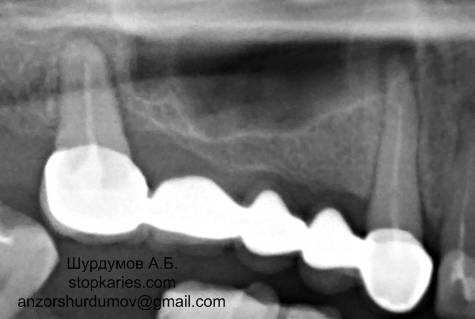

б) Почему болит зуб под пломбой? Почему болит зуб под коронкой?

Под пломбой может постепенно развиться вторичный кариес, так же может быть, что нерв давно удален и развилось воспаление тканей, окружающих зуб. Если зуб болит под коронкой – чаще всего причиной является переодонтит или радикулярная киста (см. пункты 4 и 5) Для точного диагноза нужен рентгеновский снимок.

- Переодонтит – воспаление тканей, окружающих зуб, точнее связок удерживающих зуб в костной лунке. Так же может быть острым и хроническим. Острый переодонтит отличается постоянными болями, усиливающимися при накусывании на зуб (жевании). Хронический переодонтит протекает практически без болевых ощущений, обнаруживается на рентгеновском снимке и чаще всего приходят пациенты во время обострения, жалобы такие же как и при остром процессе. Причиной может быть не леченный вовремя пульпит, травма, либо реакция на лекарства, которыми лечили зуб при пульпите.

Хронический фиброзный и гранулематозный переодонтиты на рентгенограмме